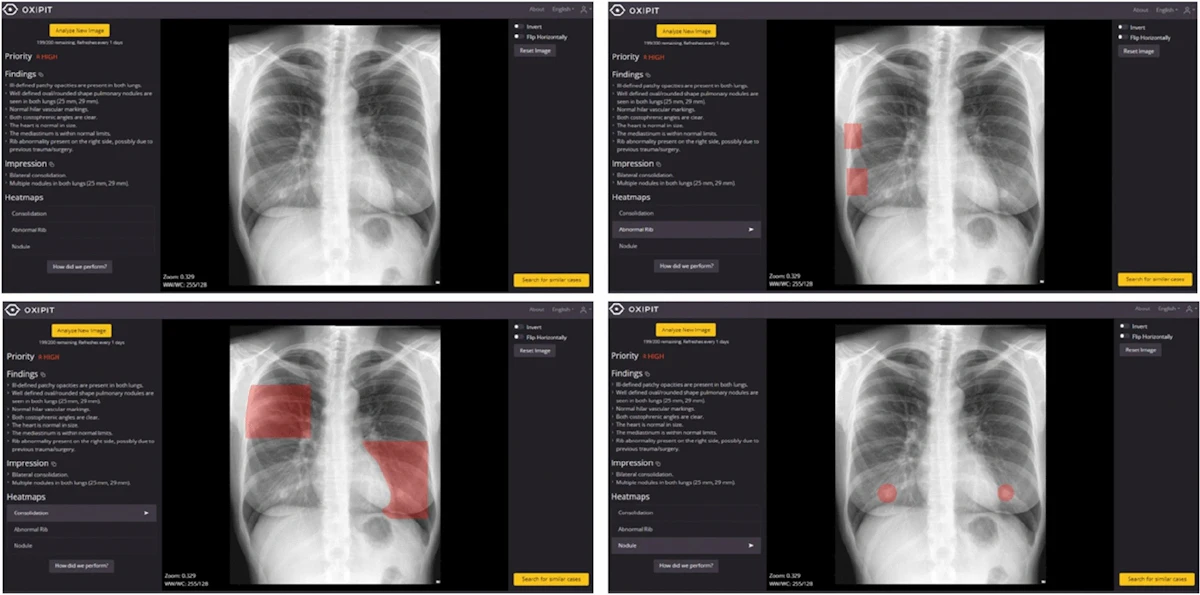

ChestEye uses a computer-aided diagnosis (CAD) algorithm that analyzes x-rays for 75 different findings and localizes the features on images as heatmaps. It can also generate preliminary text reports that incorporate relevant findings in chest x-ray images.

The algorithm was developed by a Lithuanian company called Oxipit and was trained on more than 300,000 images during its development, the authors noted.